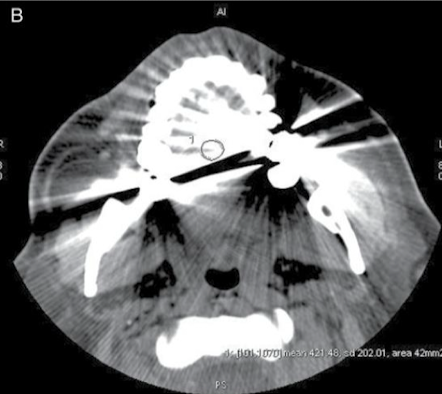

Why is this ROI not appropriate?

Beam hardening incl in ROI → SD = 202.01